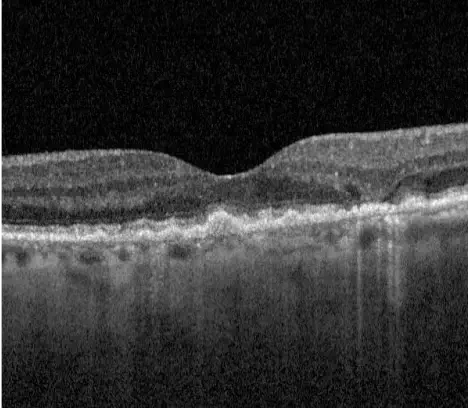

Neovascular AMD

- In clinical trials, use of IZERVAY was associated with increased rates of neovascular (wet) AMD or choroidal neovascularization (7% when administered monthly and 4% in the sham group) by Month 12. Over 24 months, the rate of neovascular (wet) AMD or choroidal neovascularization in the GATHER2 trial was 12% in the IZERVAY group and 9% in the sham group. Patients receiving IZERVAY should be monitored for signs of neovascular AMD.